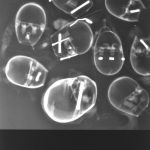

Distanced from the actual procedures (at the time) I was able to study these images for what they were. The half-familiar and recognizable bony structures, barium meal enemas, brain and body scans which became mingled with my X-rays of exotic flowers, fruit and vegetables (dipped in barium meal) plus dolls limbs and heads.

Similarities were seen between a pepper and a text book heart, a bundle of parsley and cerebral blood vessels. Dislocated dolls heads and limbs became floating body parts.